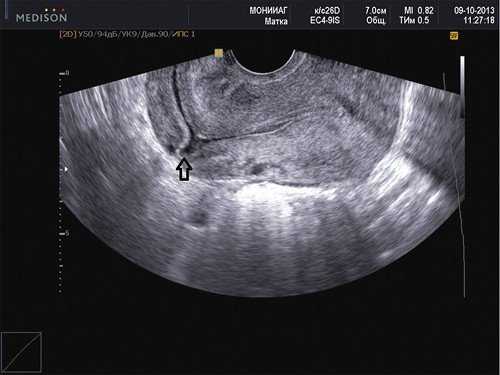

Наиболее популярная теория возникновения данного состояния заключается в том, что плодное яйцо проникает в миометрий через микроскопическое расхождение краев рубца (рис. 1).

Рис. 1. Несостоятельный рубец на матке. Стрелкой помечена ниша со стороны полости в области рубца после кесарева сечения.